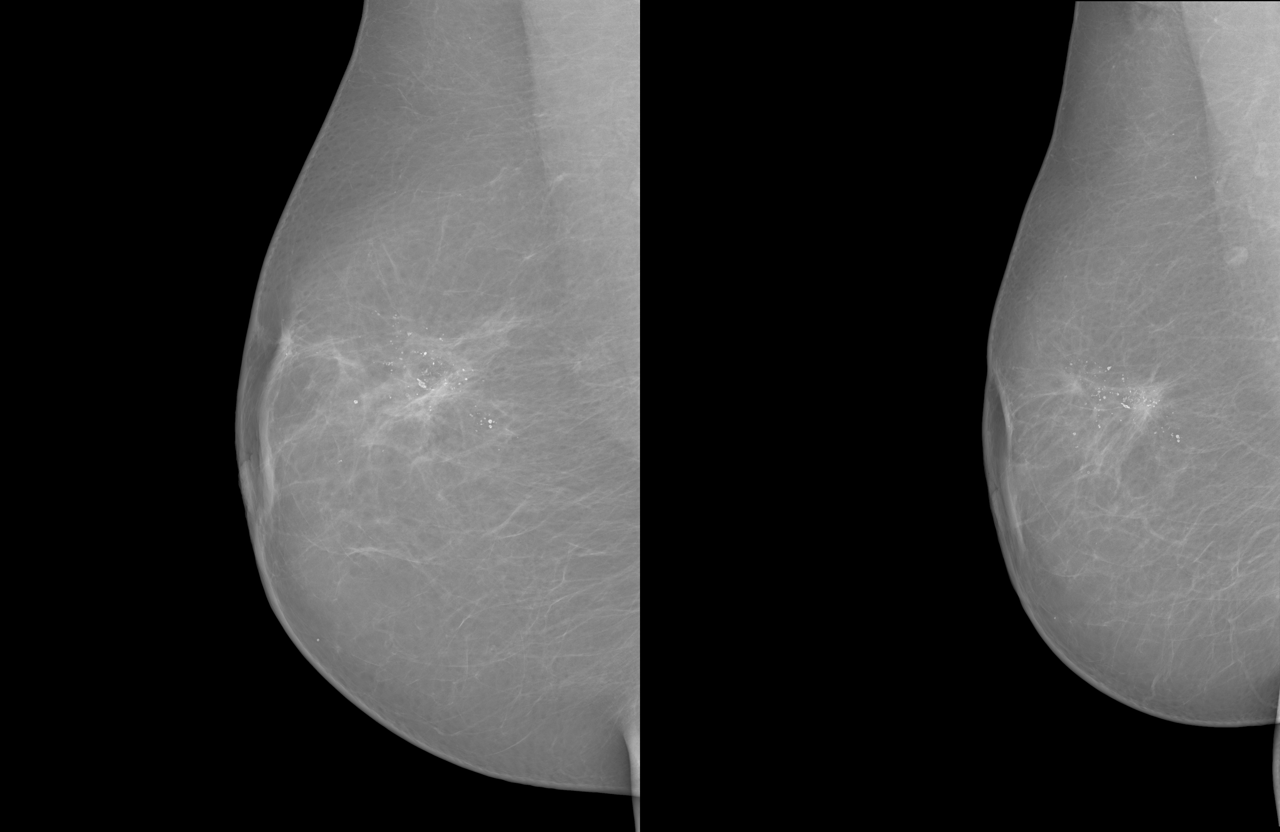

Refer to caption

(a) INBreast, R-MLO projection

(b) KAU-BCMD, R-CC projection

(c) RSNA, L-MLO projection

Figure 2: Example of a registration-ready image pair from each source dataset included in MGRegBench: (left) INBreast, (center) KAU-BCMD, and (right) RSNA. Each pair shows the same breast (left or right) in the same projection (CC or MLO) acquired during separate screening exams.

Our MGRegBench dataset is composed of mammographic images sourced from 3 publicly available datasets: INbreast [InBreast], KAU-BCMD [KAU-BCMD], and RSNA [RSNA] (image pairs examples are shown in Figure 2).

The registration evaluation set was carefully selected to closely match the training set in terms of key clinical and imaging characteristics. Specifically, the distributions of breast density and patient age (Figure 3) are approximately balanced between the two subsets. Breast density refers to the proportion of fibroglandular tissue relative to fatty tissue in the breast, a key radiological characteristic that influences both cancer risk and mammographic interpretability [spak2017bi]. Examples of breasts with different densities are shown in Figure 2. The breast in the left image has a density of 1, while in the right it has a density of 4. The density classifications in our dataset use the original notation from the metadata (levels 1-4), which map to the A-D categories in [spak2017bi]. Furthermore, the evaluation set contains an equal representation of all four standard mammographic views: R-MLO, R-CC, L-MLO, and L-CC, ensuring view-wise fairness in performance assessment.